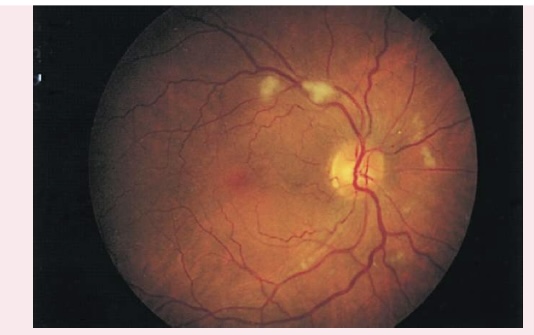

COTTON WOOL PATCHES

Also known as soft exudates, cotton wool patches have a fluffy cotton ball appearance, with irregular edges.

Appear as white or gray moderately-sized spots on retinal background

Caused by arteriole microinfarction

Associated with diabetes mellitus and hypertension